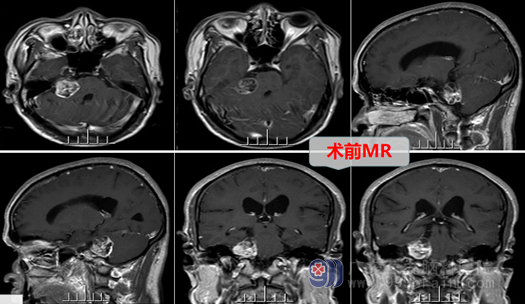

入院后,MR检查提示:右侧桥小脑角区囊实性占位:考虑听神经瘤(也称前庭神经鞘瘤)。主管医生告诉梁大叔及其家人,他的肿瘤位桥小脑角(脑干边上),手术风险较大,术后易发生并发症和后遗症;但是如果不手术,肿瘤继续生长会压迫脑干及更多神经,甚至会危及生命。梁大叔当然还是希望能够做手术切除肿瘤。

经完善术前准备排除手术禁忌症后,欧阳教授带领外十科医生团队制定了详细的手术计划,决定在全麻下为梁大叔实施:右侧桥小脑角区占位(肿瘤)切除术。手术中在显微镜放大下进行,术中可见肿瘤位于右侧桥小脑角,右侧耳蜗神经、面神经位于肿瘤前下方,三叉神经位于肿瘤上方,经仔细分离,面神经、三叉神经、舌咽神经等虽受肿瘤压迫明显,但均被保留完整,肿瘤全切。术后梁大叔返回监护室接受照护,生命体征平稳,对答正确,能够遵嘱活动。